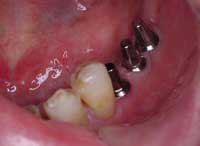

| 術前 | ソケットリフト手術 | 術後2年歯根周囲骨造成良好 |